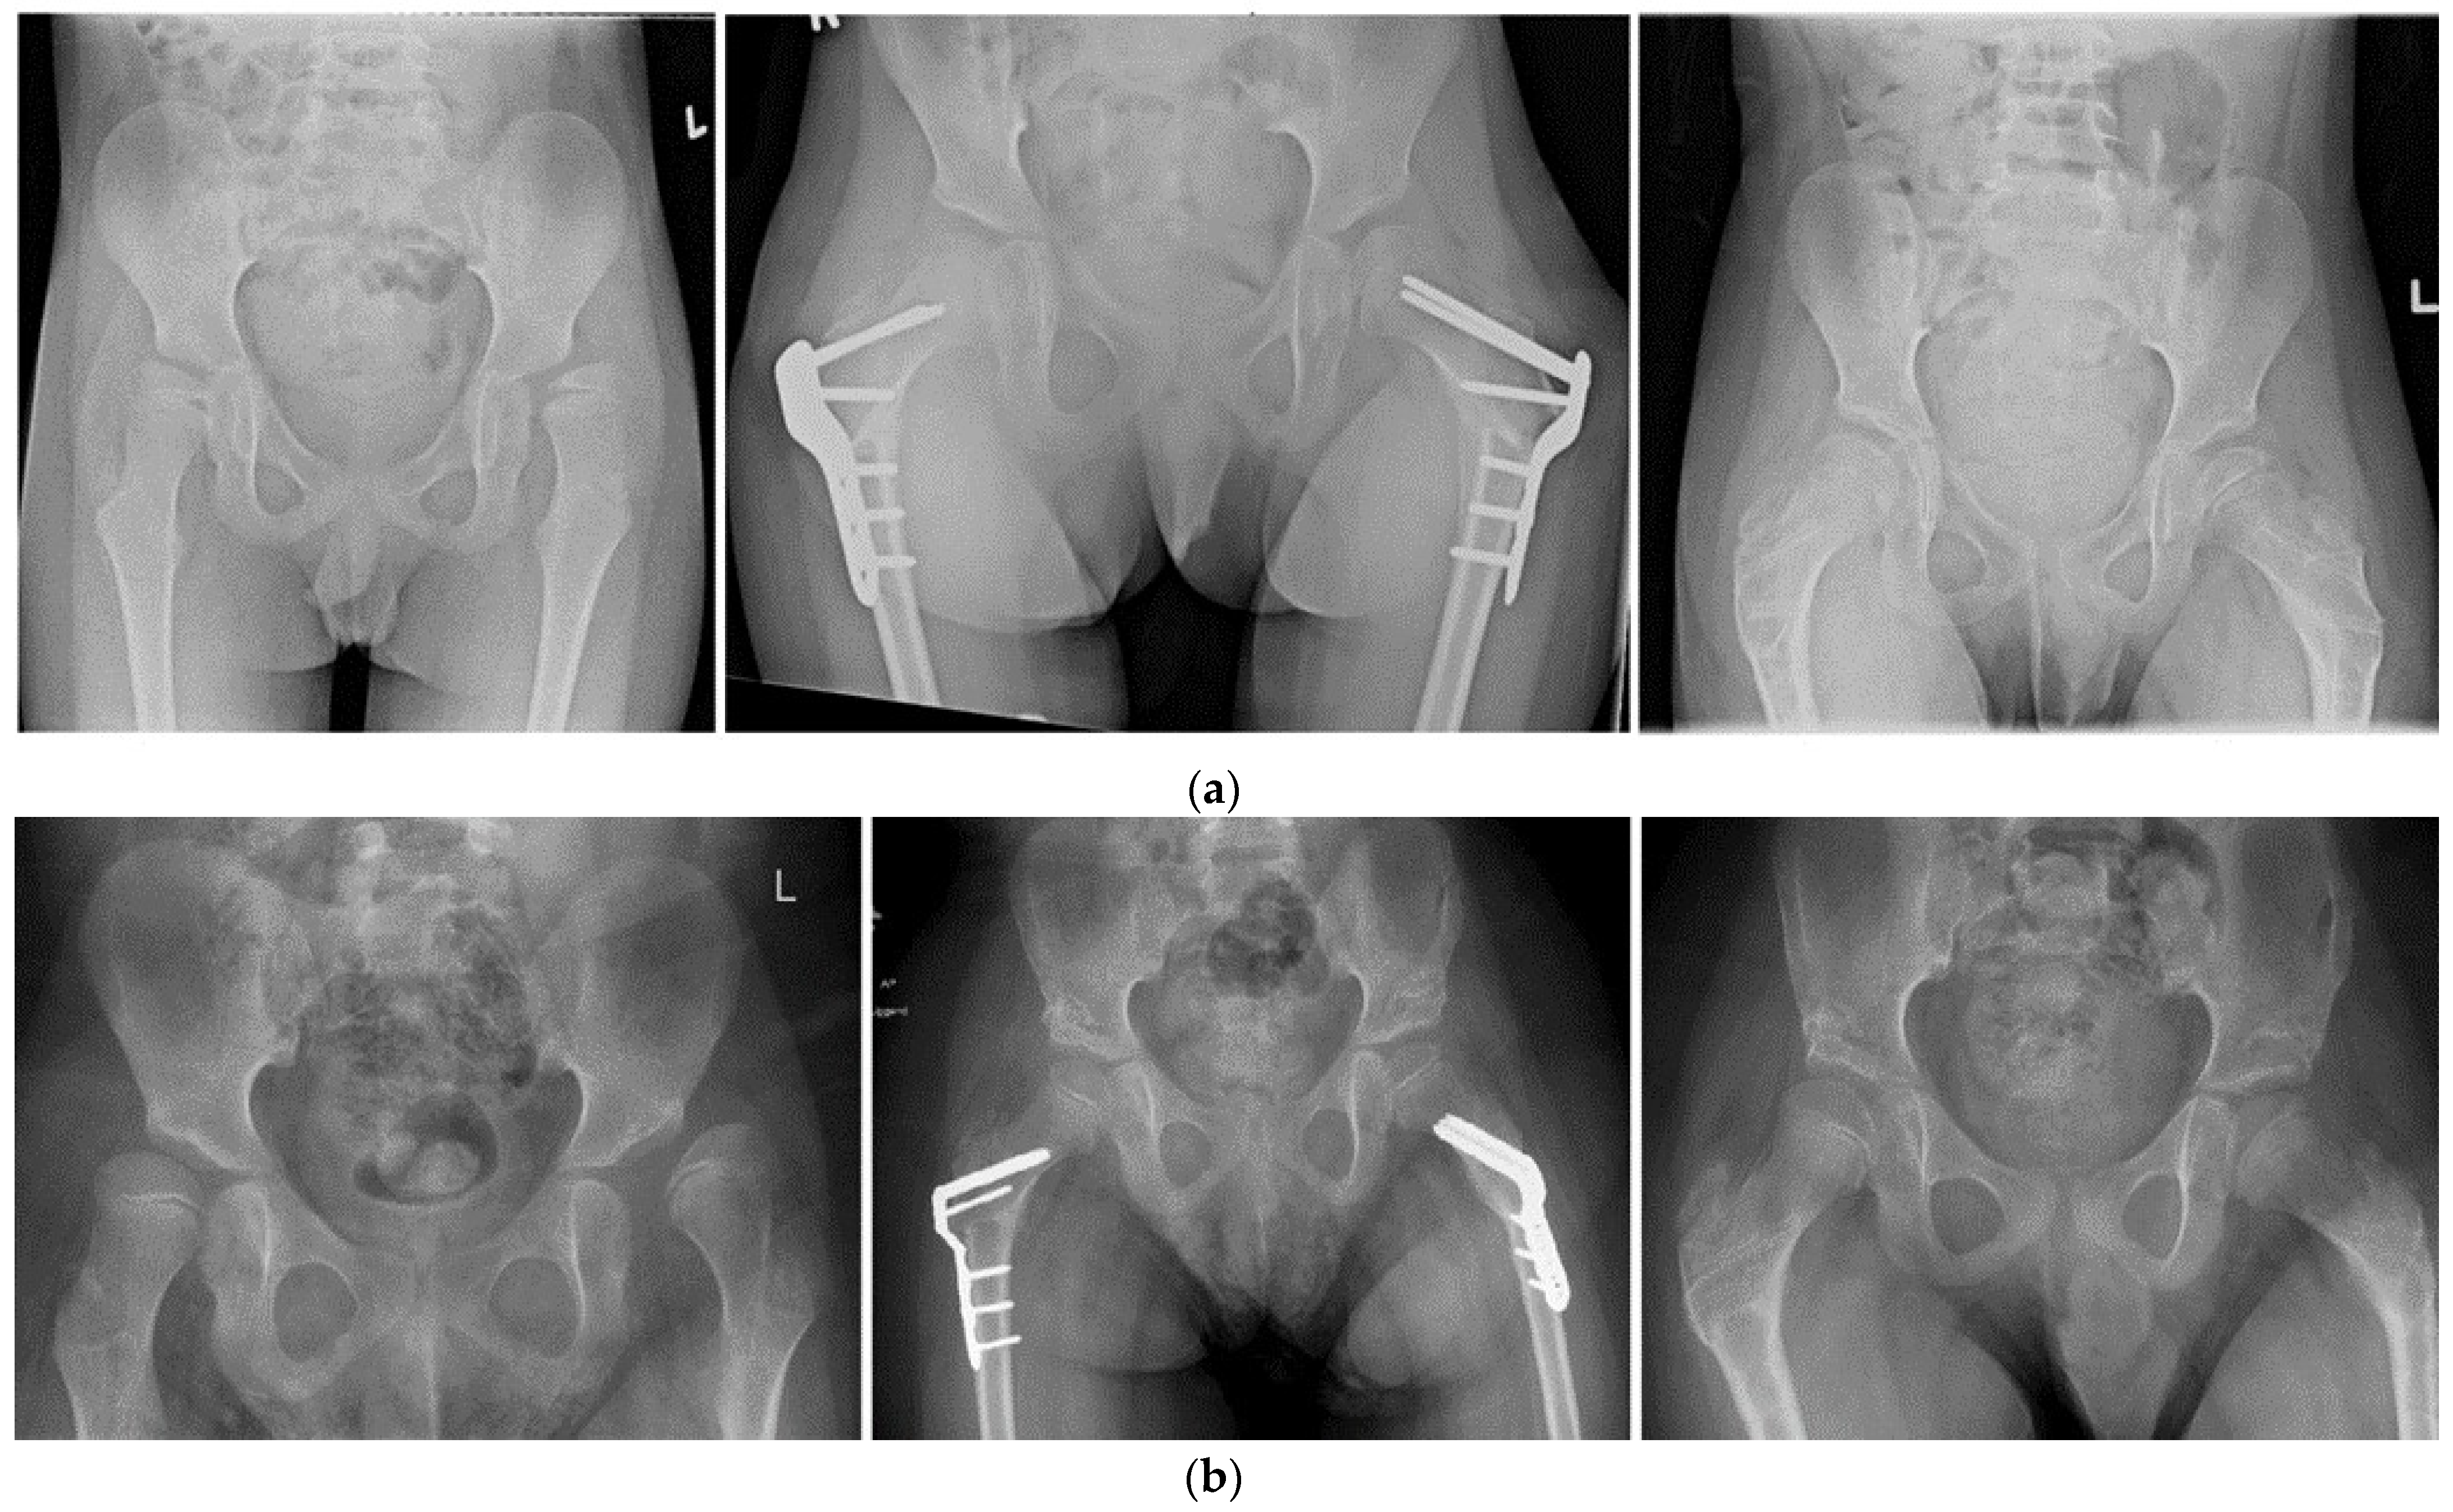

3. Results

3.3. Hip Development

3.3.2. Migration Percentage Stratified by Year of Surgery

3.4. Melbourne Cerebral Palsy Hip Classification System

4. Discussion